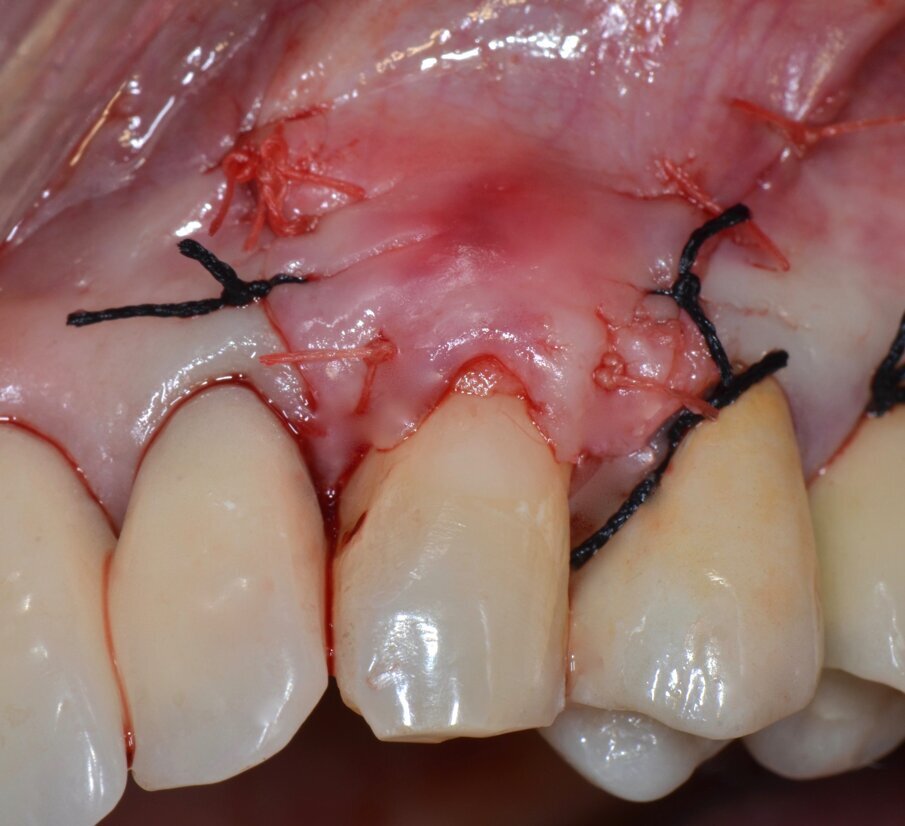

Dopo circa un mese viene eseguito un lembo a scorrimento coronale con innesto di tessuto connettivo (CAF+CTG) prelevato dal palato con la “Tecnica di Langer e Langer mod. J.Bruno” per coprire la recessione sul canino superiore sinistro e ispessire il tessuto sopra il quale verrà posizionata una faccetta in ceramica (Figg. 12-17). A due mesi dal CAF+CTG si può notare la maturazione dell’innesto con un ottimale spessore mantenuto e lo spazio guadagnato sul canino controlaterale con la ORS (Figg. 18, 19).